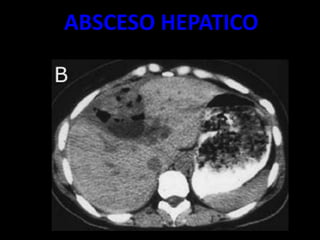

ABSCESO HEPATICO

• LESIÓN POR LO GENERAL BIEN DELIMITADA

• DENSIDAD SUELE SER ALGO SUPERIOR A LA DEL

AGUA (20-30 UH).

• TRAS LA INYECCIÓN DE CONTRASTE INTRAVENOSO

MUESTRA UNA INTENSA CAPTACIÓN ANULAR QUE ES

MUY CARACTERÍSTICA AUNQUE NO

PATOGNOMÓNICA

• UN BAJO PORCENTAJE DE ABSCESOS HEPÁTICOS

CONTIENEN GAS EN SU INTERIOR.

• EN TC

– SENSIBLE 90 %

– MASAS REDONDEADAS

– BAJA ATENUACIÒN C/S CONTRASTE

– ATENUACIÒN ENTRE 0 Y 45 UH.

– COALECER.

– NIVELES HIDROAEREOS. (INTESTINO/ABSCESO)